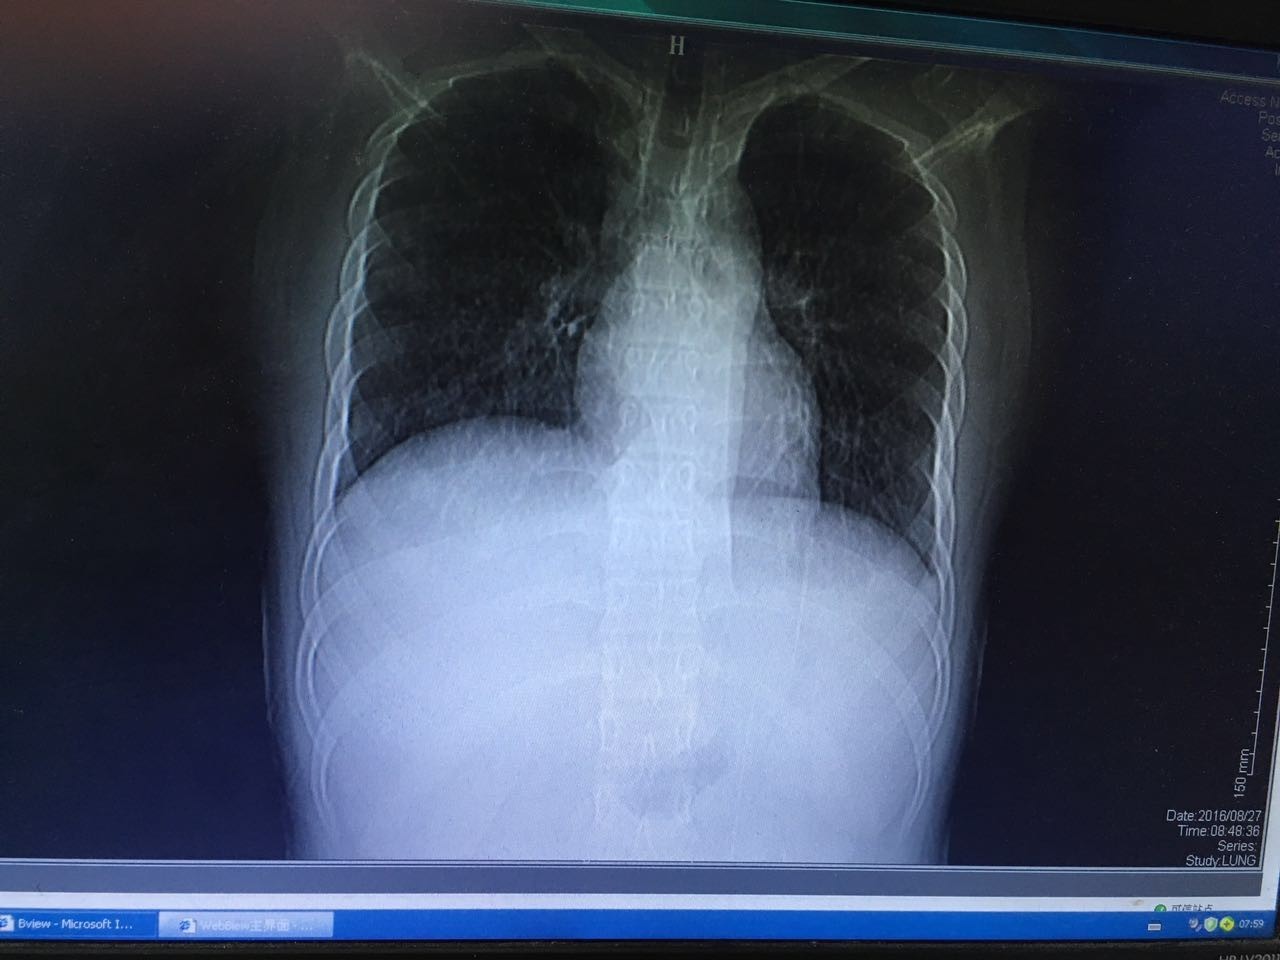

最后患者在治疗的过程中,联系了两位曾经和他在小河里摸鱼的朋友,居然都在高热。一个因为病情较重,已经转往省级医疗机构……治疗经过不详。还有一个因为肺部感染就住在我院呼吸科,我们后来接手了呼吸科的患者,也给 他完善了肠镜检查,获得了同样的结论。两人的肺部病灶及肠镜表现虽然轻重不同,但是基本上是类似的。(图片6-10)

图6